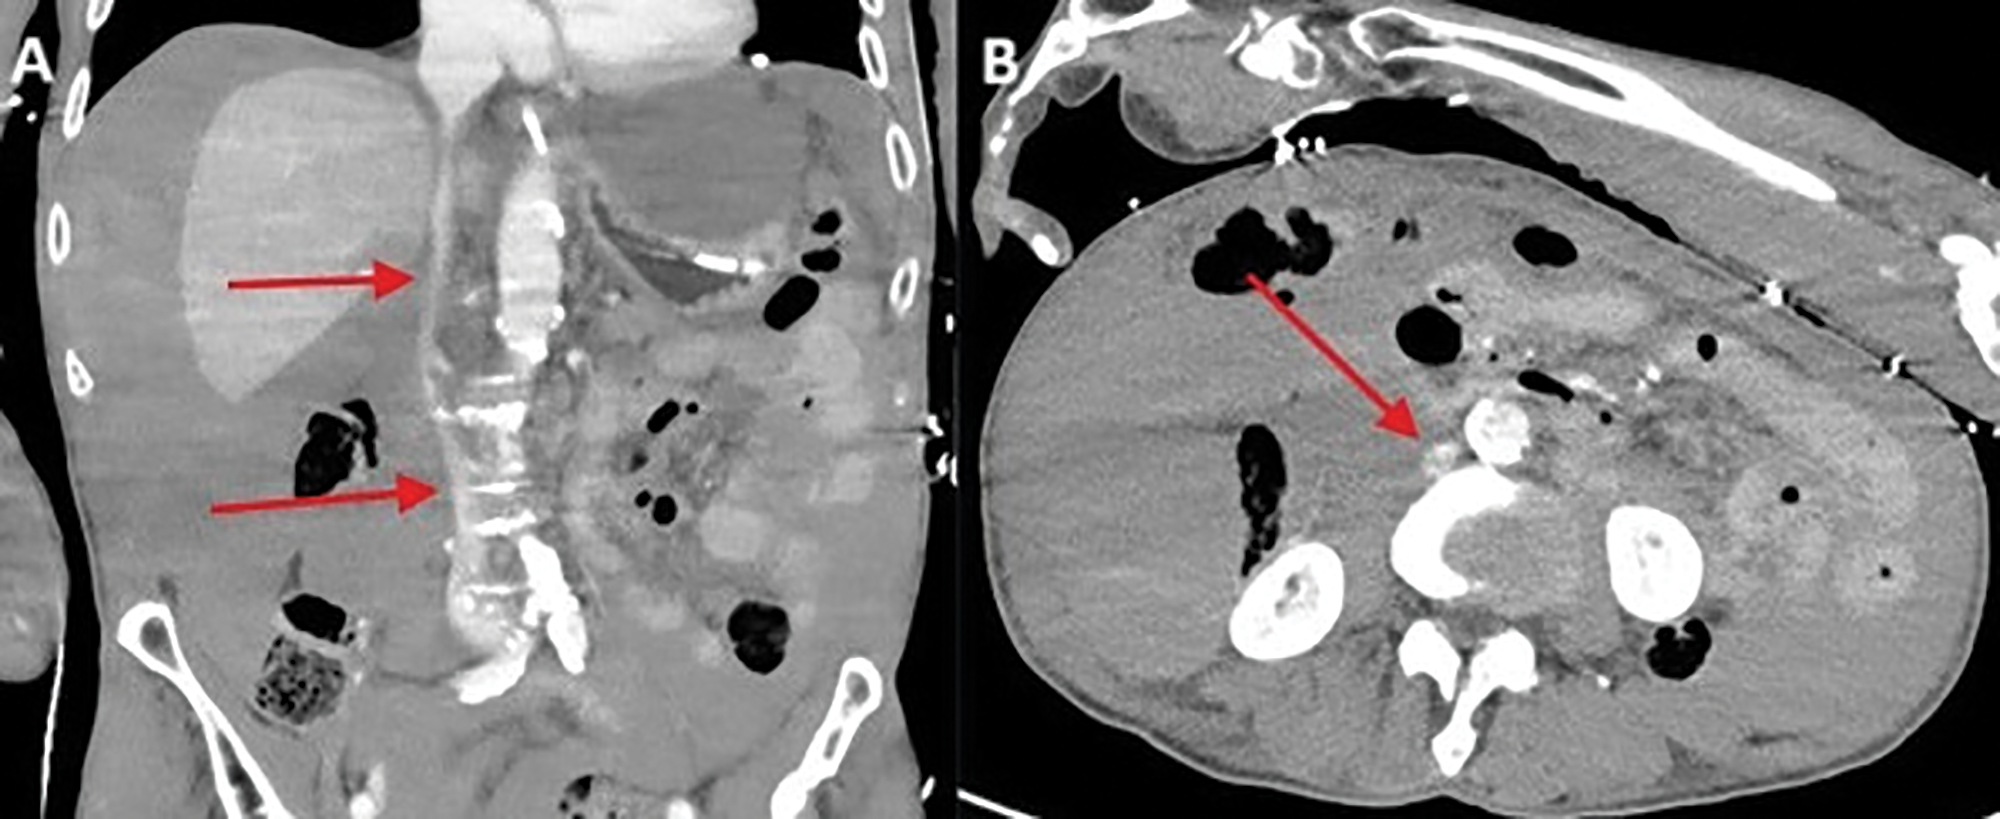

A large amount of blood was present intraperitoneally. In addition, the inferior vena cava and the major pelvic veins appeared gracile consistent with hypovolemic shock (Figure 3 A, B; red arrow). The patient’s condition further worsened with a fatal outcome a few hours later.

Figure 3

Gracile appearance of the inferior vena cava and the major pelvic veins.